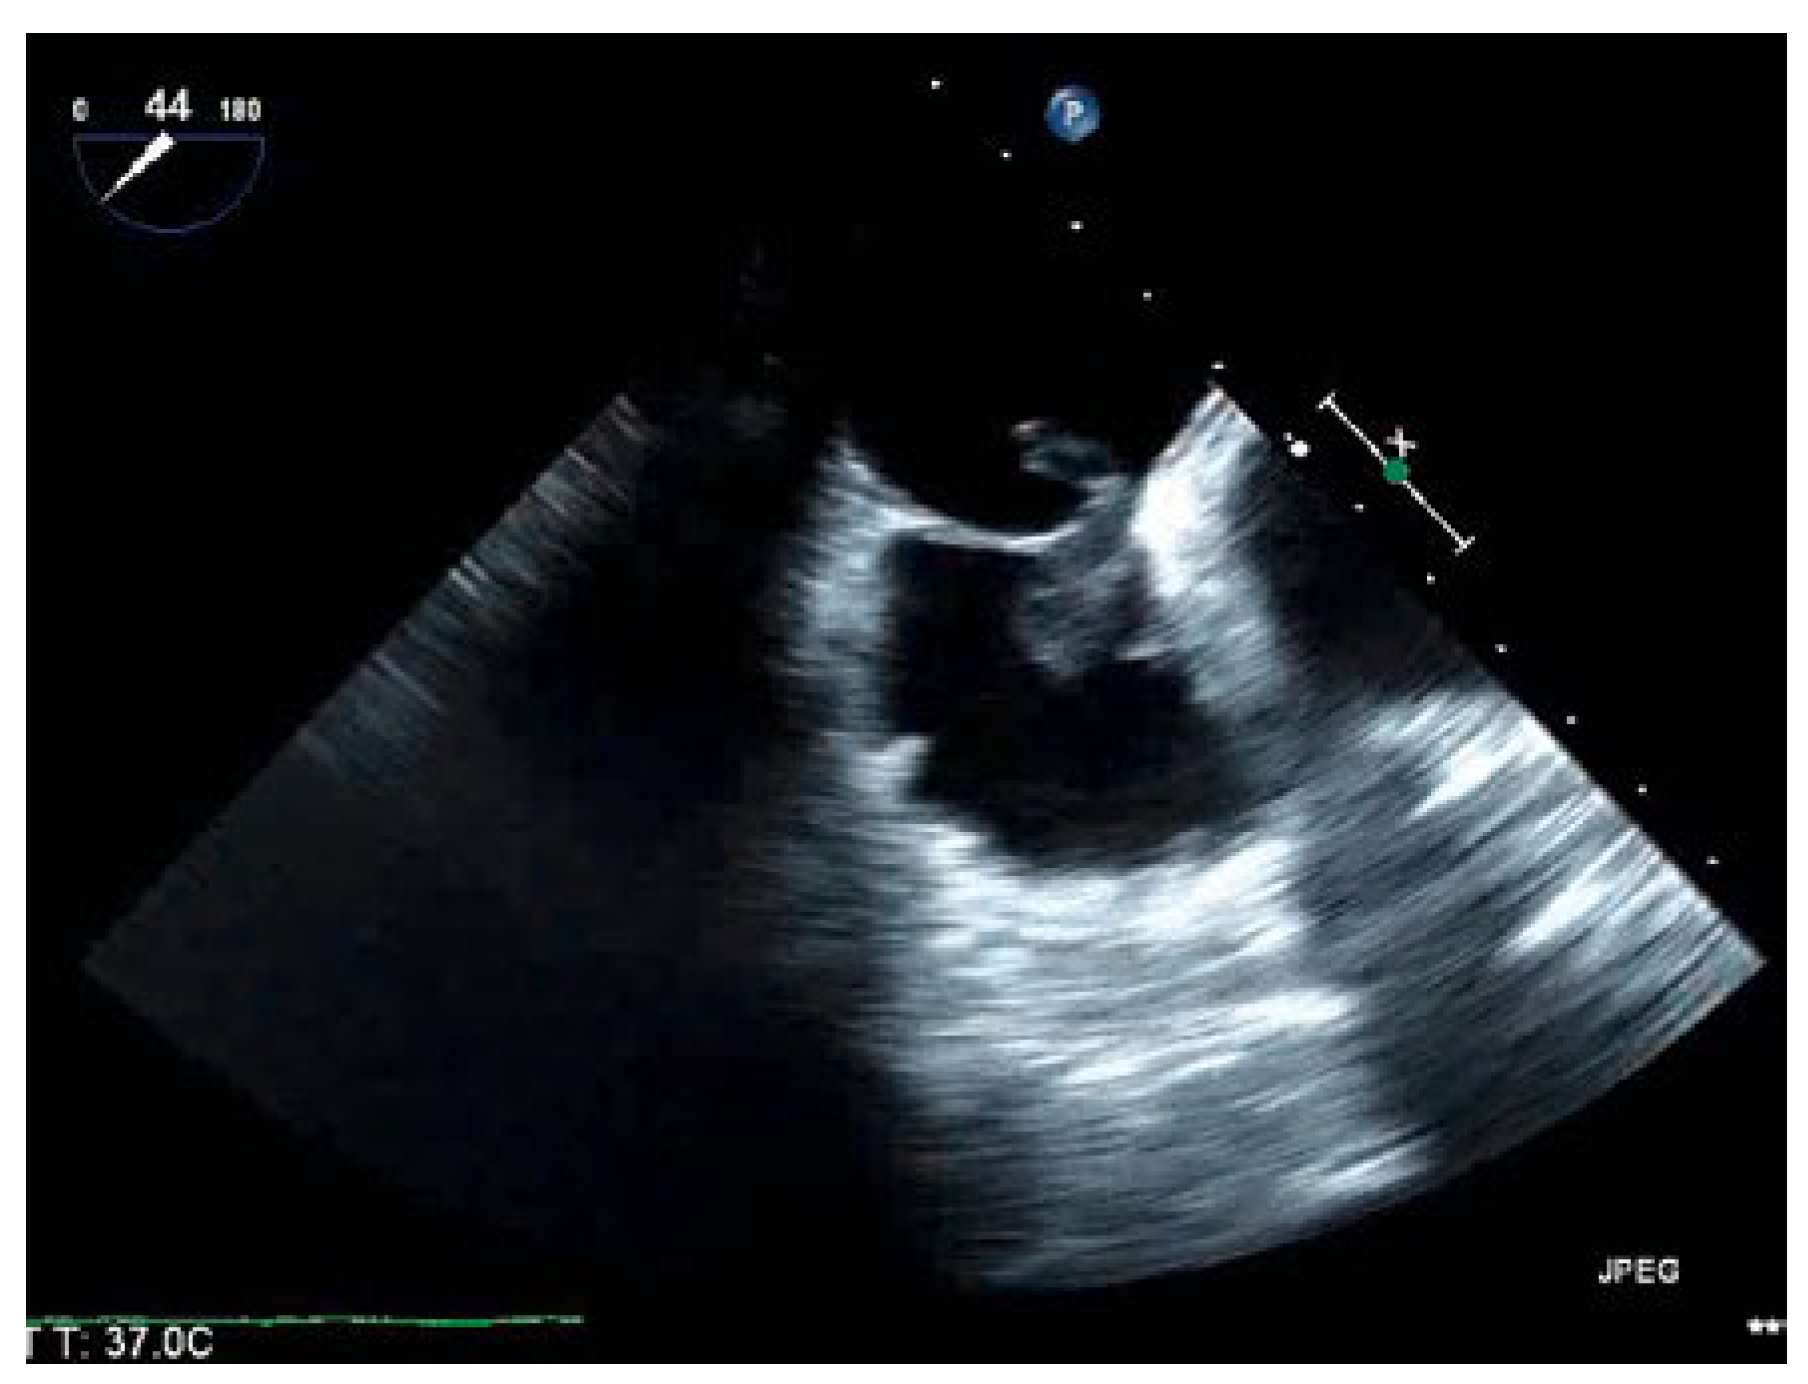

Thrombus in Transit

Case presentation